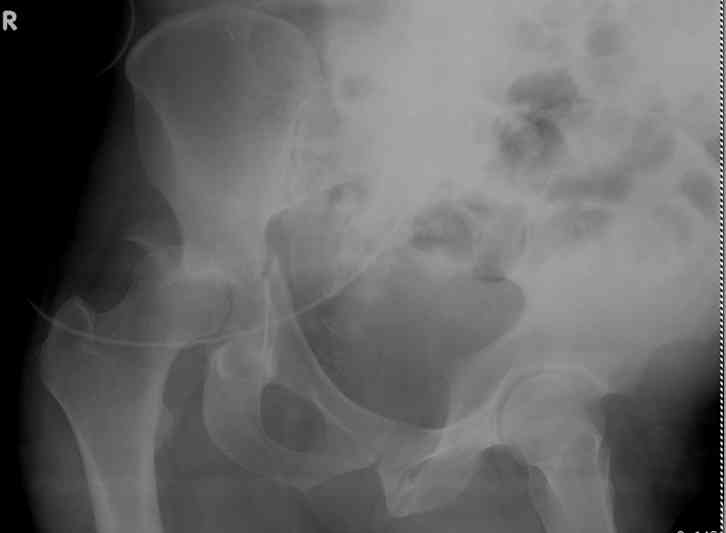

45 yo male in MVA, only other injury=small subarrachnoid bleed (neurologically fine, GCS never <14), with this transverse & associated posterior wall fx-dislocation 7/7

Pt has a history of prior abdominal surgery in Colombia (gastric bypass for obesity -- now <200 lbs).

In skeletal traction thru distal femoral pin 40 lbs with decent reduction - except for the free fragments in the hip joint. ORIF planned for post-injury day 11.

to ORIF the posterior wall Fx, kocher approach is obviously planned, which will also easily allow excision of loose bodies from the joint.

would anyone do an additional ilioinguinal approach or would you do everything posteriorly? what about surgical timing? is it affected by the loose bone frags in the joint? would anyone do this ORIF urgently?